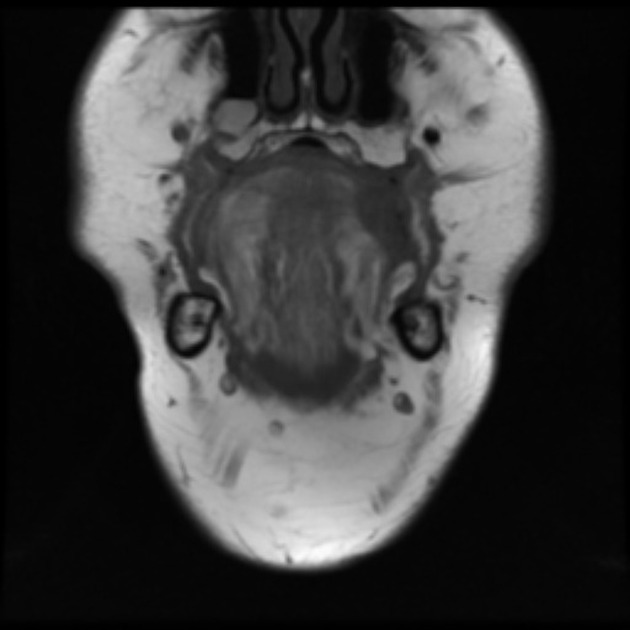

From medizzy.com

Effect of tongue piercing on gums MEDizzy Tongue Piercing Mri So what would happen if you forgot to take out an earring? So i'm having an mri done on friday on my knee and the technician said that i have to take my tongue jewelry out. Particularly fresh piercings that can’t safely be removed, or surface piercings like microdermals and surface bars? The magnets found in an mri machine are. Tongue Piercing Mri.